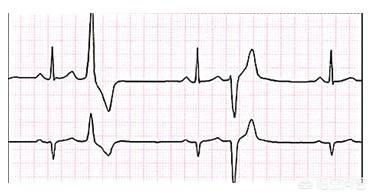

正常でない早発性心室拍動はいくつあるか?

早発性心室収縮はわが国で最も一般的な不整脈である。早発性心室拍動の回数が正常かどうかについてはコンセンサスはなく、一般に正常の場合は早発性心室拍動の総数が100回/24時間以下であり、100回/24時間を超えると頻回の早発性心室拍動とみなされる。しかし、治療の必要性や心室性期外収縮の重症度は、期外収縮の総数だけで判断すべきではない。心室細動の引き金となる期外収縮が1回の人もいれば、1日に数千回、数万回の期外収縮があっても全く問題のない人もいる。

また、早発性心室収縮の治療は、症状の有無、他の疾患の有無、他の全身状態との関連で判断する必要がある。

心室性期外収縮は機能性と器質性に分類される。機能性心室性期外収縮は、身体診察や心臓超音波検査では正常に見えるものである。このタイプは若年者に多く、自律神経機能の異常と関連している可能性があり、労作、飲酒、満腹、精神的ストレスなどによって誘発されることが多い。パニック発作などの症状がなければ治療の必要はなく、生活習慣の改善が可能です。症状がある場合は、ベタルシルなどのβ遮断薬を服用します。

- 器質性早発性心室拍動は、冠動脈疾患、高血圧、心筋症、心臓弁膜症などの心臓の構造的疾患を伴う心臓の早発性心室拍動である。これらのタイプの早発性心室拍動は一般に、症状の有無にかかわらず治療が必要である。しかし、主な焦点は原疾患の治療である。抗不整脈薬も同様にβ遮断薬よりも優先される。